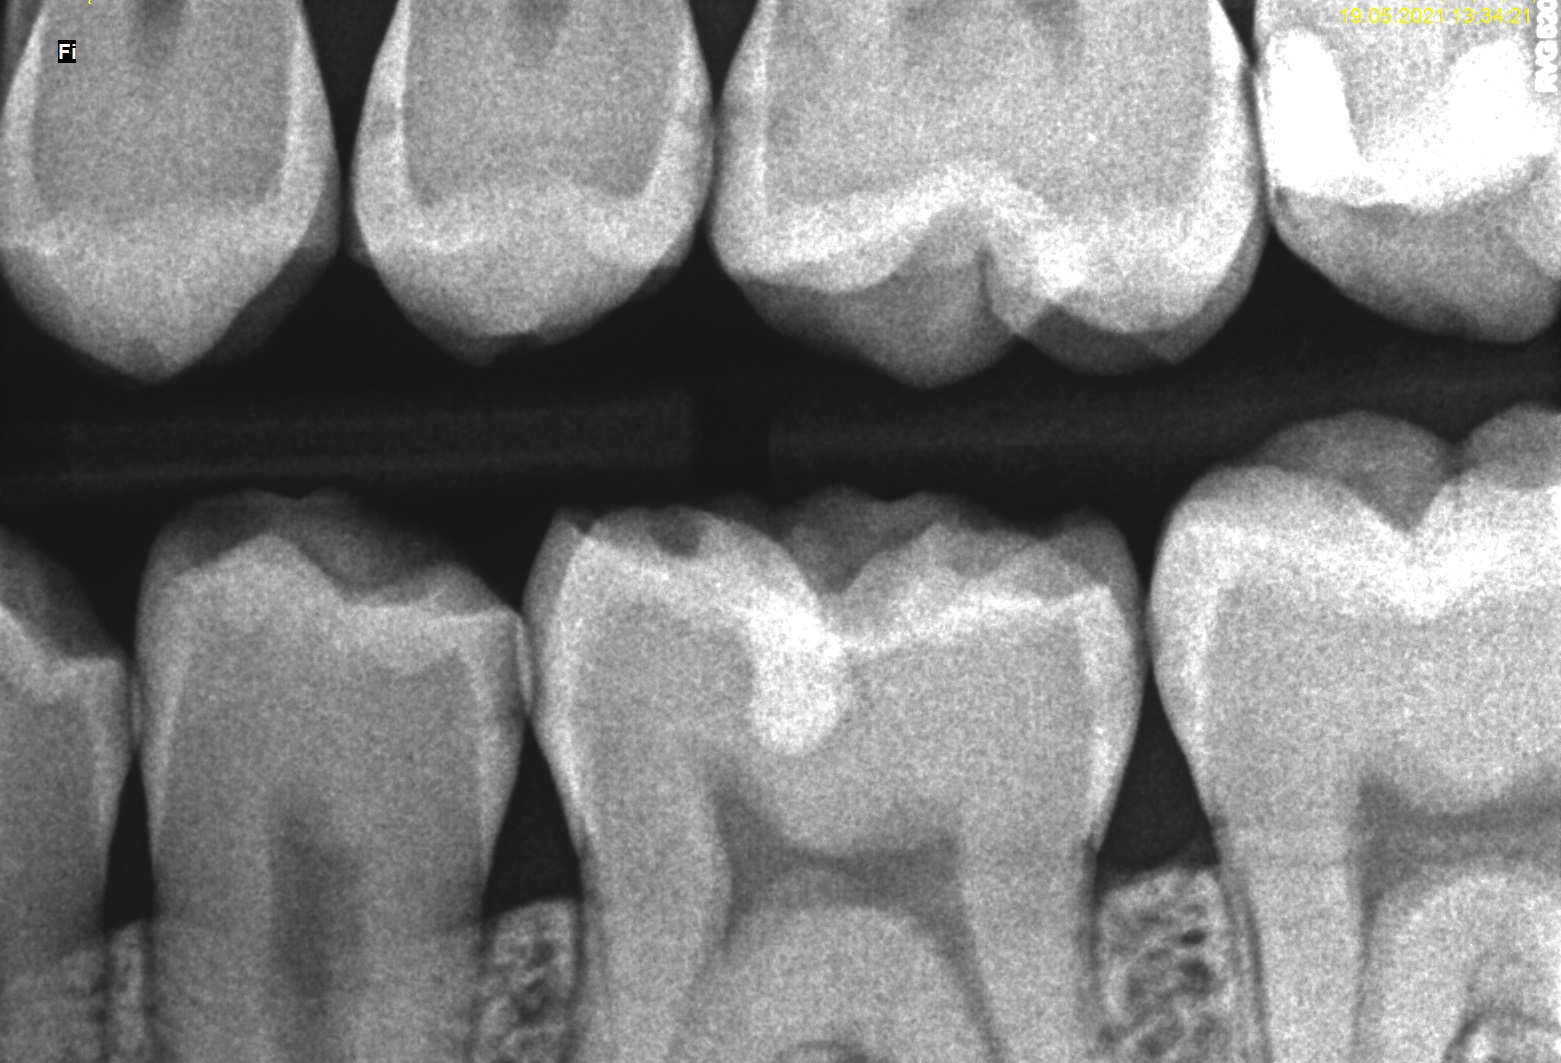

W celu oceny rozległości ubytków klasy II, diagnostykę poszerzono o zdjęcia zgryzowo‑skrzydłowe (ryc. 5 i 6). W zębie 15 dystalnie zdiagnozowano ubytek głębokości D2, mezjalnie E2, w zębie 14 dystalnie D1.

Ryc. 5. Zdjęcie skrzydłowo‑zgryzowe – strona prawa.

Ryc. 6. Zdjęcie skrzydłowo‑zgryzowe – strona lewa.